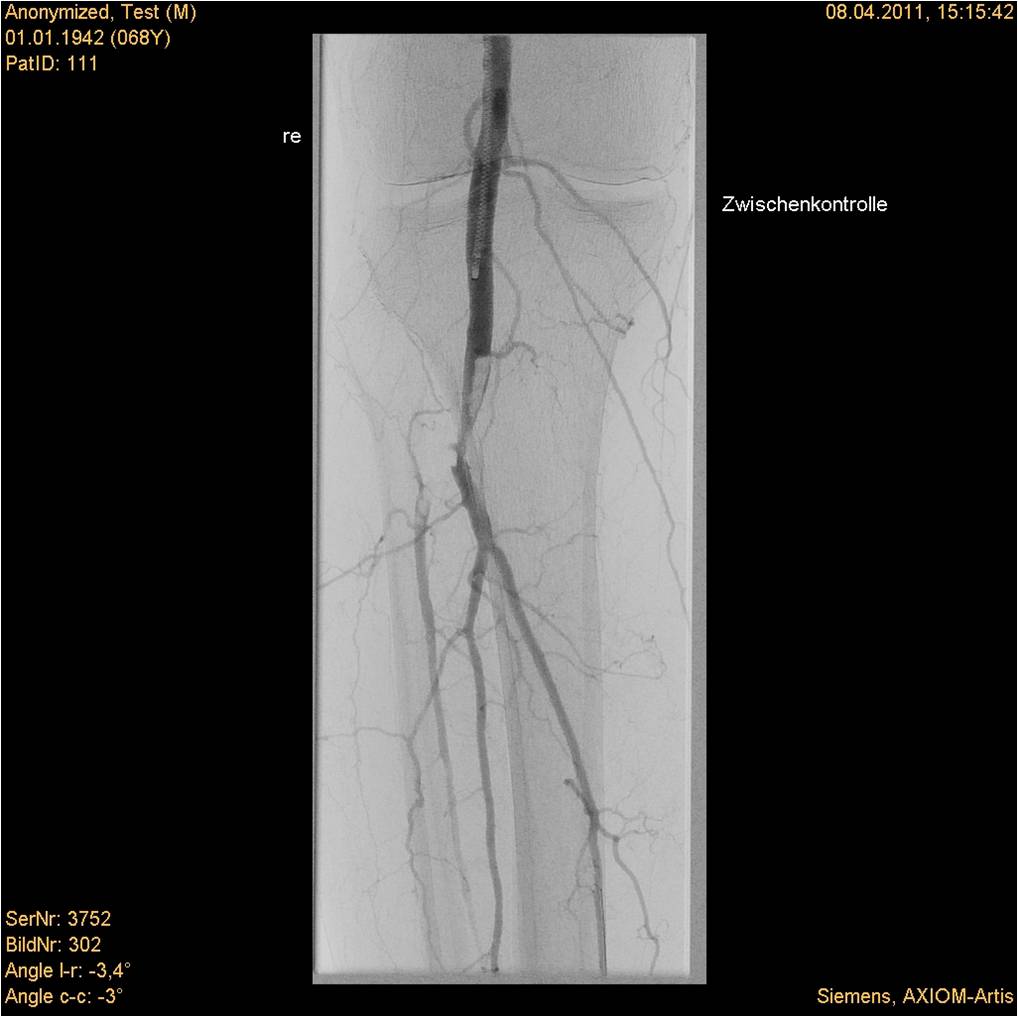

Rotarex®S导管和Straub医疗动力系统配合使用,用于除心肺、冠状动脉和脑循环之外的血管内新鲜、亚急性和慢性阻塞中的血栓、血栓栓塞物和动脉粥样硬化物质的经皮腔内切除。可应用于由动脉粥样硬化、血栓合并栓子、单纯血栓形成所致自体动脉、支架内、旁路血管及透析造瘘血管内的急慢性血栓。

Rotarex®S腔内旋吸导管和Aspirex®S血栓抽吸导管已成为国际上治疗动静脉闭塞性疾病的重要治疗方法之一。随着CFDA证书的获批,中国的外周血管介入专家可使用该腔内导管系统为其病人治疗各种不同的血管闭塞性疾病。自2008年Rotarex®S腔内旋吸导管和Aspirex®S血栓抽吸导管在瑞士上市以来,Straub血栓抽吸术已在国外得到广泛应用。经临床验证安全、可靠、高效。